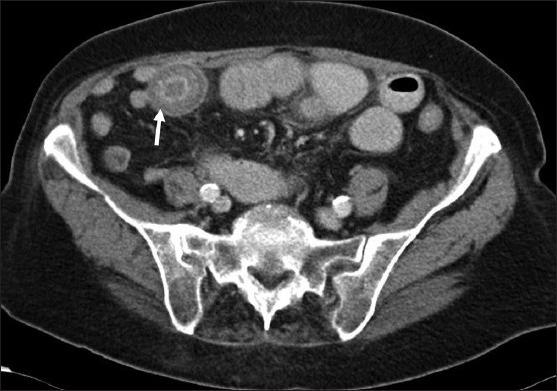

Gallstones ileus is an uncommon cause but important cause of small bowel obstruction. The gallstone enters the intestinal lumen via a fistula located in the duodenum (cholecystoduodenal), or rarely, in the colon (cholecystocolonic) or stomach (cholecystogastric). This may result in large bowel or gastric outlet obstruction (Bouveret's Syndrome). Gallstone ileus affects the elderly females pre-dominantly and is associated with a high morbidity and mortality rate if diagnosis and urgent surgical intervention are delayed. In this paper, we report on the case of an elderly lady who presented with classical symptoms and signs of small bowel obstruction. She was subsequently diagnosed with gallstone ileus due to a large gallstones lodged in the intestinal lumen. We perform a literature review on this rare disease and discuss the two main surgical approaches in managing this condition. Gallstone ileus should be considered in the differential diagnosis of small bowel obstruction especially in elderly women who have no history of abdominal surgery or abdominal hernia. Early intervention is important because of the high mortality rate due to the poor general condition that often exists in this subgroup of patients. There is no general consensus on gold standard surgical approach in these cases but a two-stage procedure (either enterotomy alone or enterotomy and subsequent cholecystectomy) has been shown to be associated with lower mortality rates.

胆石性肠梗阻是小肠梗阻的一种罕见但重要的病因。胆结石通过位于十二指肠的瘘管(胆囊十二指肠瘘)进入肠腔,或极少情况下通过位于结肠的瘘管(胆囊结肠瘘)或胃的瘘管(胆囊胃瘘)进入。这可能导致大肠或胃出口梗阻(布维耶综合征)。胆石性肠梗阻主要影响老年女性,如果诊断和紧急手术干预延迟,其发病率和死亡率较高。在本文中,我们报告了一例出现小肠梗阻典型症状和体征的老年女性病例。她随后被诊断为胆石性肠梗阻,原因是一枚大的胆结石嵌顿在肠腔内。我们对这种罕见疾病进行了文献综述,并讨论了治疗这种疾病的两种主要手术方法。在小肠梗阻的鉴别诊断中应考虑胆石性肠梗阻,尤其是在没有腹部手术或腹外疝病史的老年女性中。由于这类患者通常身体状况较差,死亡率较高,因此早期干预很重要。对于这些病例的金标准手术方法尚无普遍共识,但两阶段手术(单独肠切开术或肠切开术及随后的胆囊切除术)已被证明与较低的死亡率相关。